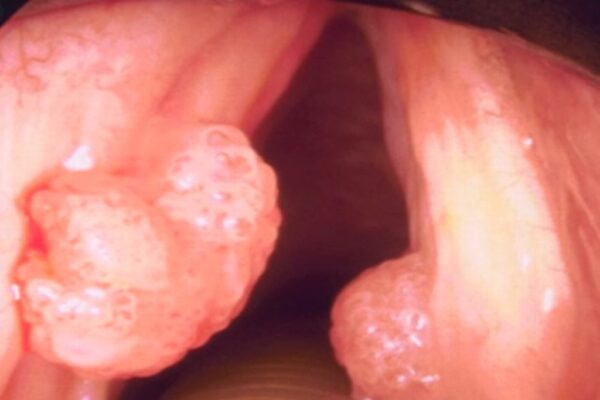

La Papilomatosis Respiratoria Recurrente (PRR) es una condición caracterizada por la formación de papilomas en la laringe y otras áreas del tracto respiratorio donde se encuentran epitelios ciliados y escamosos. Los papilomas son crecimientos benignos que pueden obstruir las vías respiratorias y causar síntomas como ronquera, dificultad para respirar y en casos graves, dificultad respiratoria severa.

Esta condición es diferenciada de los papilomas orales debido a su tendencia a volverse sintomática y recurrente. Los pacientes con PRR experimentan episodios recurrentes de crecimiento de papilomas en las vías respiratorias, lo cual puede resultar en deterioro progresivo de la función respiratoria si no se trata adecuadamente.

La manifestación clínica de la PRR varía desde casos leves con ronquera intermitente hasta situaciones más severas con obstrucción completa de las vías respiratorias. La frecuencia y gravedad de los episodios de papilomatosis pueden estar influenciados por factores como la respuesta inmune del individuo, la carga viral, y la ubicación específica de los papilomas dentro del tracto respiratorio.